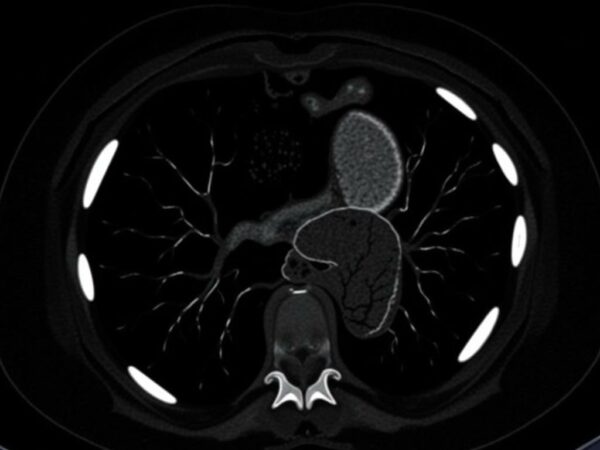

КТ печени часто проводят с внутривенным контрастом. Контраст вводят шприцем-автоматом, и снимки делают в нескольких фазах — каждая занимает своё время и показывает разные свойства тканей. Понимание этих фаз помогает понимать, почему врач смотрит не на один снимок, а на серию.

Обычно используют три-четыре фазы: до контраста (нативная), артериальная, портальная (венозная) и отложенная. Нативная фаза полезна для оценки кальцинатов и кровоизлияний. Артериальная фаза выявляет гиперваскулярные новообразования. Портальная фаза — основная для обнаружения метастазов и многих опухолей. Отложенная фаза помогает отличать некоторые доброкачественные образования от злокачественных по характеру накопления и вымывания контраста.

| Нативная | До введения контраста | Кальцинаты, интенсивность по плотности, кровоизлияния |

| Артериальная | Через короткое время после инъекции | Гиперваскулярные опухоли, артерии |

| Портальная | Через большее время — когда контраст в воротной вене | Метастазы, большинство опухолей, паренхима |

| Отложенная | Через 5–10 минут | Замедленное накопление/вымывание контраста, характеристики очагов |

На КТ различают кисты, гемангиомы, фокальную узловую гиперплазию, гепатоцеллюлярную карциному (ГЦК), метастазы и абсцессы. Каждое образование имеет характерное поведение в разных фазах контрастирования, и опытный рентгенолог может по картинке заподозрить диагноз ещё до пункции.

- Гемангиома часто демонстрирует характерное постепенное заполнение контраста с периферии к центру.

- Фокальная узловая гиперплазия может иметь центральный рубец и интенсивное артериальное усиление.

- ГЦК часто гиперваскулярен в артериальную фазу и меняет контрастность в последующих фазах.